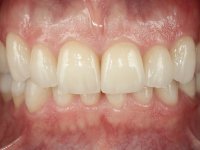

Paciente do sexo masculino, com 36 anos, não fumador. Fez tratamento ortodôntico e reabilitou esteticamente o sector anterior com restaurações em resina composta. As restaurações apresentavam um aumento vertical médio de 2 mm em relação o bordo incisal. Apresentavam-se esteticamente satisfatórias, mas com algumas fraturas incisais. O dente 1.5 apresentava um processo apical e o dente 2.6 apresentava tratamento endodôntico e uma lesão endo-periodontal. No maxilar inferior no local do dente 3.5 apresentava um implante com uma coroa aparafusada e o dente 8.5 ainda estava presente em boca com agenesia do dente 4.5. O paciente apresentava uma ligeira perda da dimensão vertical da oclusão provavelmente associada a um visível desgaste das superfícies oclusais. O periodonto era espesso e apresentava uma excelente higiene oral.

Após análise clínica e imagiológica foi proposto ao paciente recuperar a dimensão vertical da oclusão essencialmente à custa de incrementos oclusais inferiores utilizando “overlays” no sector posterior e facetas no sector anterior. A coroa aparafusada sobre o implante 3.5 seria substituída, no sentido de acompanhar este incremento. Na maxila o dente 2.6 teria extração indicada e posteriormente seria reabilitado com um implante e respetiva coroa. No sentido de reabilitar esteticamente o paciente duma forma minimamente invasiva, foi proposta a colocação de facetas feldespáticas no sector antero-superior. O objetivo de aumentar ligeiramente a D.V.O., teria como função “proteger” eficazmente o sector antero-superior.

Realizado o diagnóstico e tomada a decisão quanto ao tratamento a executar, tornou-se importante definir qual a sequência de trabalho a adotar no sentido de conseguir a reabilitação da D.V.O. (V.D.O), de forma progressiva e equilibrada. Na primeira fase fez-se uma pré-impressão da arcada inferior com silicone tipo “putty” e em seguida realizou-se o preparo dentário de todo o sector posterior. O preparo para os overlays foi feito coronalmente à linha amelo cementaria no sentido de ser o mais conservador possível. A impressão foi feita com técnica de dupla mistura após afastamento gengival realizado com pasta de caulino. A provisória foi realizada com resina composta de polimerização dual. Em laboratório foram realizados os overlays após se ter aberto ligeiramente (1,5mm) a D.V.O. nos modelos montados em articulador semi-ajustável. Simultaneamente o sector antero-inferior foi encerado no sentido de acompanhar este aumento da D.V.O. Também foi confecionada uma chave de silicone translucido para posterior confeção dos provisórios antero-inferiores. Em boca foi primeiro realizada a provisionalização dos dentes anteriores utilizando resina composta previamente aquecida após preparação das superfícies dentárias para a adesão. Foi colocado o dique de borracha para promover o isolamento absoluto e posteriormente foram colados os overlays. Em laboratório foi realizada nova chave de silicone para confecionar os provisórios antero-superiores. Seguidamente em boca foram preparados os seis dentes antero-superiores após colocação do fio de afastamento gengival. Feita a preparação adequada das superfícies dentárias foi realizada a impressão com técnica de dupla mistura e a respetiva provisória. Em laboratório foram confecionadas 6 facetas feldespáticas num modelo de trabalho tipo “Geller”. A provisória foi removida e as facetas foram coladas em boca utilizando um isolamento relativo competente. Esta opção foi tomada em virtude de uma prévia experiencia negativa com a colocação do dique de borracha na mandibula. Após a colagem dos laminados antero-superiores foram dadas 12 semanas para avaliar a adaptação do paciente à nova situação e então iniciar a confeção das facetas antero-inferiores. Após colocação do fio de afastamento gengival. foram feitos os preparos dentários adequados e em seguida foi feita a impressão. Também foi feita a preparação do dente 3.4 que, entretanto, tinha sofrido uma fratura do overlay. As facetas e a restauração do 3.4 foram realizadas num modelo de trabalho tipo “Geller”. Após remoção da provisória, as facetas foram coladas em boca, utilizando um isolamento relativo pelas razões apontadas anteriormente. Após colocação do trabalho o paciente foi reabilitado por outros colegas com um implante na zona do 2.6 e substituição da coroa aparafusada sobre o implante colocado no local do 3.5. Posteriormente surgiram fraturas nos overlays dos dentes 4.7 e 3.7 que foram reabilitados com overlays em Zr.